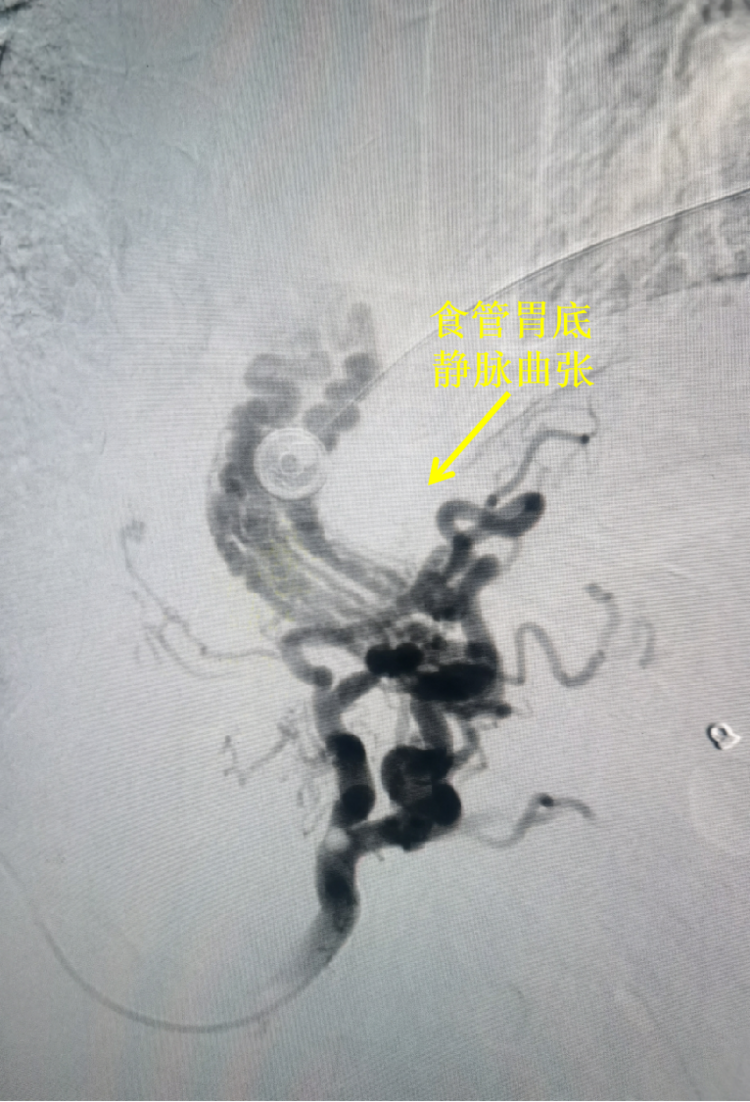

2021-11-25血管介入科救治一例肝硬化所致上消化道大出血患者

18日,我院血管介入科在刘顺帆主任带领下为一例上消化道大出血病人行经皮肝穿刺胃冠状静脉栓塞术(PTVE),术后患者停止出血,病情稳定。 患者为中年男性,因“呕血”... -